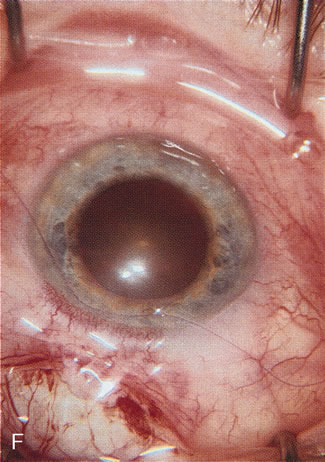

Fig. 4. Viscocanalostomy with deep sclerectomy and phacoemulsification. Nonpenetrating filtration procedures (NPFS) may be combined with phacoemulsification. Patients with mild disc damage and a history of limited topical drug therapy are the best candidates. Patients who require an IOP in the low teens are not good candidates for NPFS. By definition, NPFS is designed to lower IOP without penetrating into the anterior chamber, thereby avoiding the complications associated with trabeculectomy. Viscocanalostomy is intended to allow aqueous to percolate through a trabeculodescemetic membrane into a subscleral cavern created by the deep sclerectomy. The aqueous diffuses from the cavern into the dilated ostia of Schlemm's canal and into the episcleral venous plexus. A. Fashion a uniform 300-micron superficial scleral flap 1 mm into clear cornea. B. Construct a second 600-micron deep flap that facilitates the unroofing of Schlemm's canal, seen as the darker area. C. Use viscoelastic to dilate the ostia of Schlemm's canal. The major problem with viscocanalostomy is the eventual closure of the ostium decreasing flow to the episcleral plexus. D. Dissect the deep flap anteriorly into clear cornea creating the trabeculodescemetic membrane. This membrane is clearly seen between the scleral spur and the bend of the deep flap. The integrity of this membrane ensures the nonpenetrating portion of the surgery. Another problem with NPFS is the eventual fibrosis of this initially transparent membrane requiring goniopuncture. E. Deep sclerectomy gets its name from removal of the deep flap. Removal of this flap creates the potential subscleral space for accumulation of aqueous before it enters Schlemm's canal and exits the episcleral venous plexus. After removal of the deep flap, the superficial flap is sutured into place and conjunctiva closed. Approximately half of these procedures develop a shallow bleb.